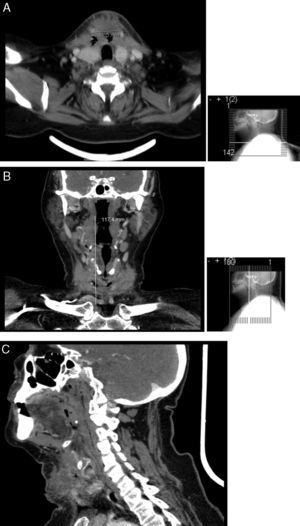

Efetuou tomografia axial computorizada (TC) cervical, que identificou abcesso parafaríngeo direito com 13mm de diâmetro, com ligeira compressão da via aérea, até ao bordo inferior do lobo direito da tiroide, com uma extensão longitudinal de cerca de 85mm; o abcesso envolvia a metade direita do osso hioide, apresentando um diâmetro máximo a este nível de 30mm. A TC revelou ainda densificação dos tecidos moles da região submentoniana, compatível com alterações inflamatórias e adenomegalias cervicais bilaterais (fig. 3).